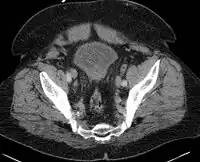

Prostatitis

Prostatitis is inflammation of the prostate gland.[1] There are two main types acute and chronic.[1] Acute prostatitis is sudden in onset, results in significant pain, and is less common.[1] Chronic prostatitis lasts for at least three months, symptoms come and go, and it is more common.[1] Complications of acute disease may include urinary retention or a prostate abscess.[1] Chronic disease may result in recurrent urinary tract infections.[2]

The cause of acute disease is generally a bacterial infection, while the cause of chronic disease is often less clear.[1] Chronic disease may be divided into chronic bacterial prostatitis and chronic prostatitis/chronic pelvic pain syndrome (CP/CPPS).[2] Another category is known as asymptomatic inflammatory prostatitis (AIP).[2] Diagnosis may involve examination, urine analysis, medical imaging, PSA testing, and semen testing.[2]